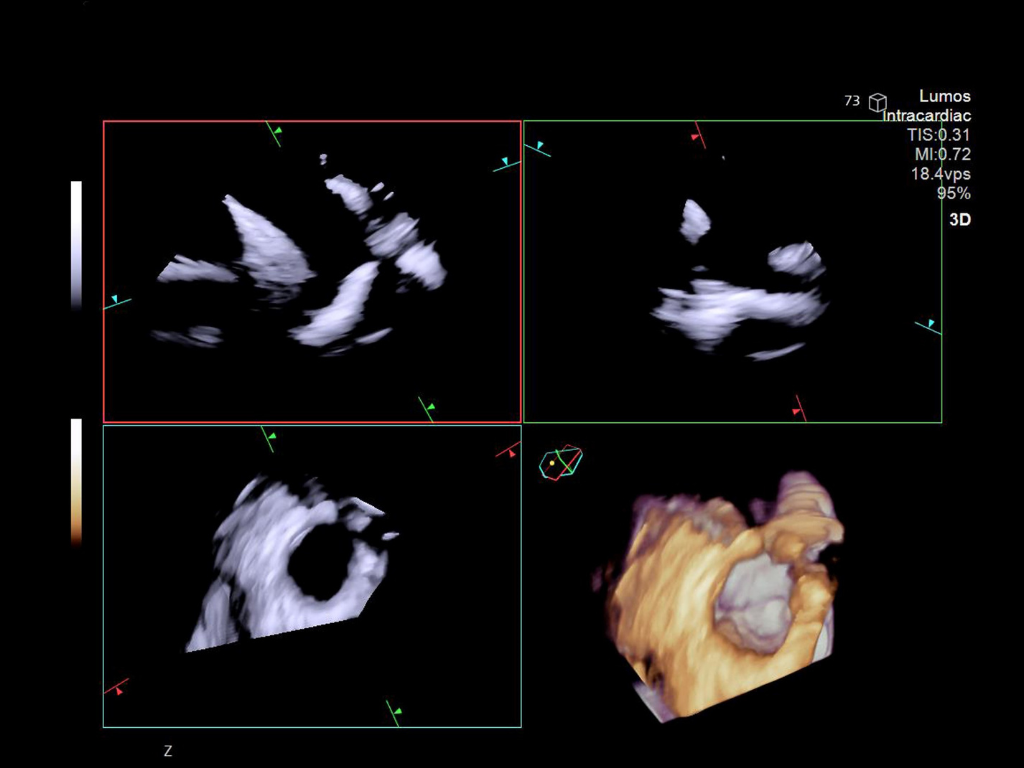

LAA Orifice

MPR view of LAA orifice